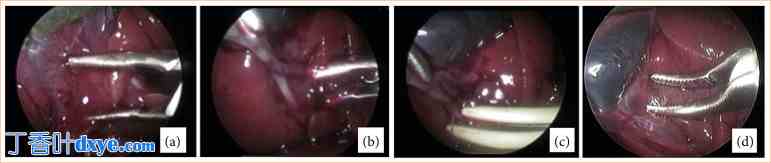

GLE 组 (n = 10) 接受 CL 技术治疗,使用标准电外科分离技术 (双极马里兰电切) 经 Calot 三角进行分离,并使用 EBVS-LigaSure 进行胆囊管阻断。在胆管周围进行两次阻断。使用 EBVS-LigaSure 钳切割功能在胆囊附近的阻断处进行胆囊管横断,在胆囊管内留下两个远端阻断点。然后,在胆囊管阻断后,使用双极马里兰电切钳沿 Calot 三角方向向胆囊底部分离胆囊与其肝床之间的腹膜附着处 (图 2)。对于提出的第二种技术,在 GLL 组 (n = 10) 中,使用 EBVS-LigaSure 经 Calot 三角进行解剖,并阻断和横断胆囊管(图 3)。

图 2. GLE 组腹腔镜胆囊切除术技术。(a) 使用 Maryland 双极解剖钳经 Calot 三角进行解剖;(b) 使用电热双极血管封闭装置进行胆囊管阻断,并在胆管周围进行两次阻断。(c) 使用电热双极血管封闭装置进行胆囊管横断。(d) 使用 Maryland 双极钳沿 Calot 三角方向向胆囊底部解剖胆囊与其肝床之间的腹膜附着处。